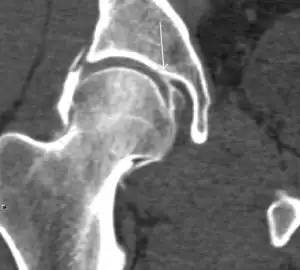

Synovial chondromatosis can be confidently diagnosed by X-ray when calcified cartilaginous chondromas are seen. However, other synovial proliferative processes, such as pigmented villonodular synovitis, require MRI for accurate diagnosis, although noncalcified synovitis can be suspected in radiographs by indirect signs, such as soft tissue swelling and/or erosions in the femoral head, femoral neck, or acetabulum (Figure 7).[1]

Figure 7:

In synovial proliferative disorders, MRI demonstrates synovial hypertrophy. In the case of PVNS, characteristic foci of low signal intensity related to hemosiderin deposition are better seen on gradient echo T2* images (Figure 7). In the case of synovial osteochondromatosis, the synovial hypertrophy is accompanied by intermediate signal cartilaginous loose bodies and/or low signal calcified loose bodies.[1]